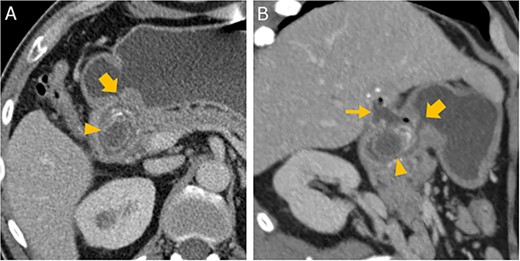

Abdominal CT in axial (A) and oblique paracoronal reconstruction (B); gallstone in the duodenal bulb (arrowhead

), pylorus (thick arrow

), chronically inflamed, and collapsed gall bladder with fistula to the duodenum (thin arrow

); image courtesy of Gerald Wolf, State Hospital Western Styria, Austria.